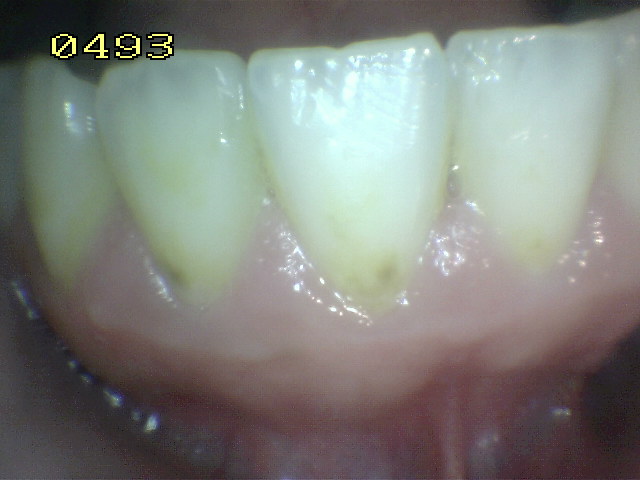

Con el fin de utilizar los criterios ICDAS en la práctica clínica las siguientes condiciones son esenciales para permitir a los examinadores evaluar cada uno de los códigos de caries con precisión:

• Remueva la placa dento-bacteriana de la superficies lisas y oclusales por medio de un cepillo dental y lave la zona con jeringa triple

• Remueva las manchas superficiales  y el cálculo dental de las superficies dentarias

• Hacer examen visual de la superficie húmeda:

3. Inicialmente el examen visual se realiza con las superficies húmedas.